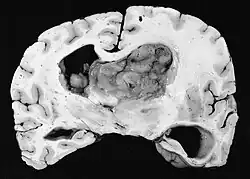

Histológicamente, son características de la lesión las células gigantes astrocíticas; sin embargo, la morfología de las células tumorales puede variar desde células poligonales con citoplasma vítreo y núcleos ganglioides hasta células fusiformes en una matriz fibrilar. Las células tumorales muestran una expresión variable de GFAP, S-100, sinaptofisina y neurofilamentos.